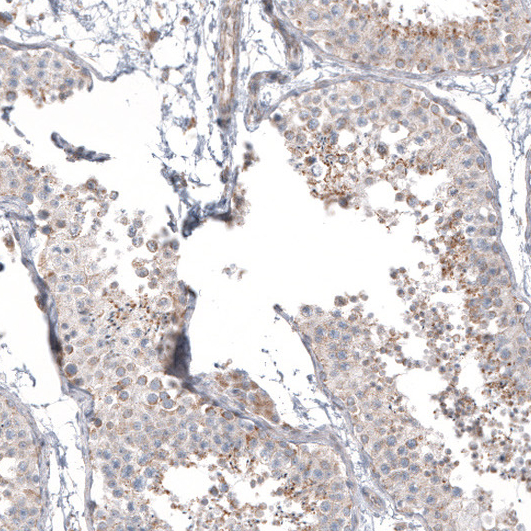

Immunohistochemical staining of human testis shows moderate granular cytoplasmic positivity in cells in seminiferous ducts.